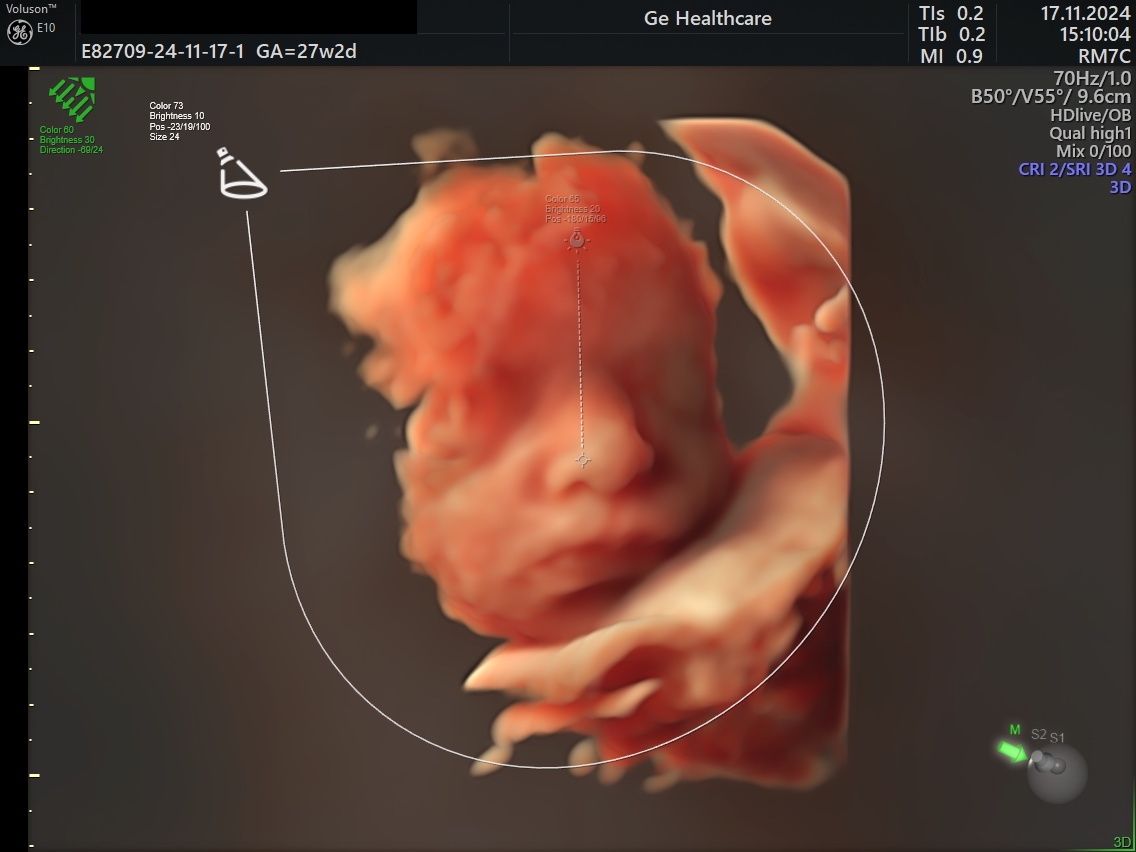

Mi impegno ad offire un'assistenza ginecologica ed ostetrica attenta, aggiornata ed umana. Ho maturato esperienza nel campo della diagnosi prenatale e mi dedico con passione all'ecografia ostetrica e ginecologica. Utilizzo un ecografo GE Voluson E10, tra i più evoluti del campo, per garantire immagini ad alta definizione.

Ecografia 3D ginecologica e ostetrica

Consiglio vivamente.• Studio Medico Dott.ssa Serena Scida • ecografia 3D ginecologica e ostetrica •

Esperienza bellissima, ero in vacanza dai miei genitori e mi sono recata dalla dottoressa per una visita di controllo devo dire visita bellissima molto scrupolosa e mi ha trasmesso molta tranquillità. Una delle visite più belle che ho fatto fino ad oggi, fossi stata giù in Calabria mi sarei fatta seguire sicuramente durante la mia gravidanza. Le immagini più belle del mio bimbo. Grazie mille Dortoressa!

• Studio Medico Dott.ssa Serena Scida • ecografia 3D ginecologica e ostetrica •